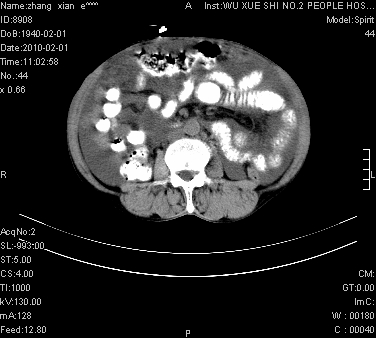

标题: CT24434:70岁 女 腹胀,腹水原因待查 [打印本页]

标题: CT24434:70岁 女 腹胀,腹水原因待查

大量腹水,脾脏囊性占位,子宫颈占位,右侧腹股沟淋巴结肿大,建议+c,先查妇科。

腹盆腔大量积液,子宫增大,子宫颈增大外形不规则,内见低密度影,膀胱后壁显示不清,右腹股沟肿大淋巴结,脾脏囊性占位,子宫颈占位,子宫颈癌?建议增强。

考虑:1、腹膜转移,大量腹水;

2、脾占位性病变;

3、左侧卵巢占位性病变,建议增强进一步检查。

考虑:1、腹膜转移,大量腹水;2、脾占位性病变;3、左侧卵巢占位性病变,建议增强进一步检查。支持